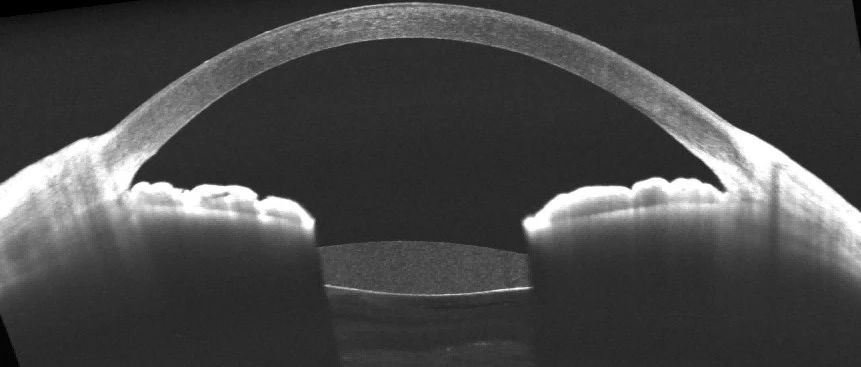

- 超乳玻切术后人工晶状体即时还是延期植入?图湃瑶光助力人工晶状体倾斜偏心研究

- 超乳玻切术后即时与延期人工晶状体植入有无偏斜差异?近期,上海爱尔眼科医院李轻宸博士,上海嘉定区中心医院眼科杨舟医生和上海市中医医院眼科刘瑞医生,运用图湃全域扫频OCT的另一款系列——瑶光·星,进行眼前节的OCT图像采集。在《Indian J...